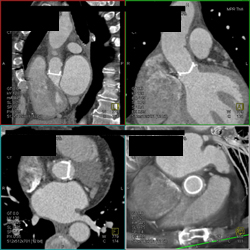

Diagnosis

Mitral Valve Replacement